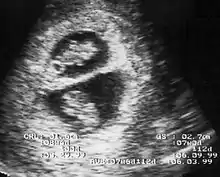

By performing an obstetric ultrasound at a gestational age of 10–14 weeks, monochorionic-diamniotic twins are discerned from dichorionic twins. The presence of a "T-sign" at the inter-twin membrane-placental junction is indicative of monochorionic-diamniotic twins (that is, the junction between the inter-twin membrane and the external rim forms a right angle), whereas dichorionic twins present with a "lambda (λ) sign" (that is, the chorion forms a wedge-shaped protrusion into the inter-twin space, creating a rather curved junction).[4] The "lambda sign" is also called the "twin peak sign". At ultrasound at a gestational age of 16–20 weeks, the "lambda sign" is indicative of dichorionicity but its absence does not exclude it.[5]